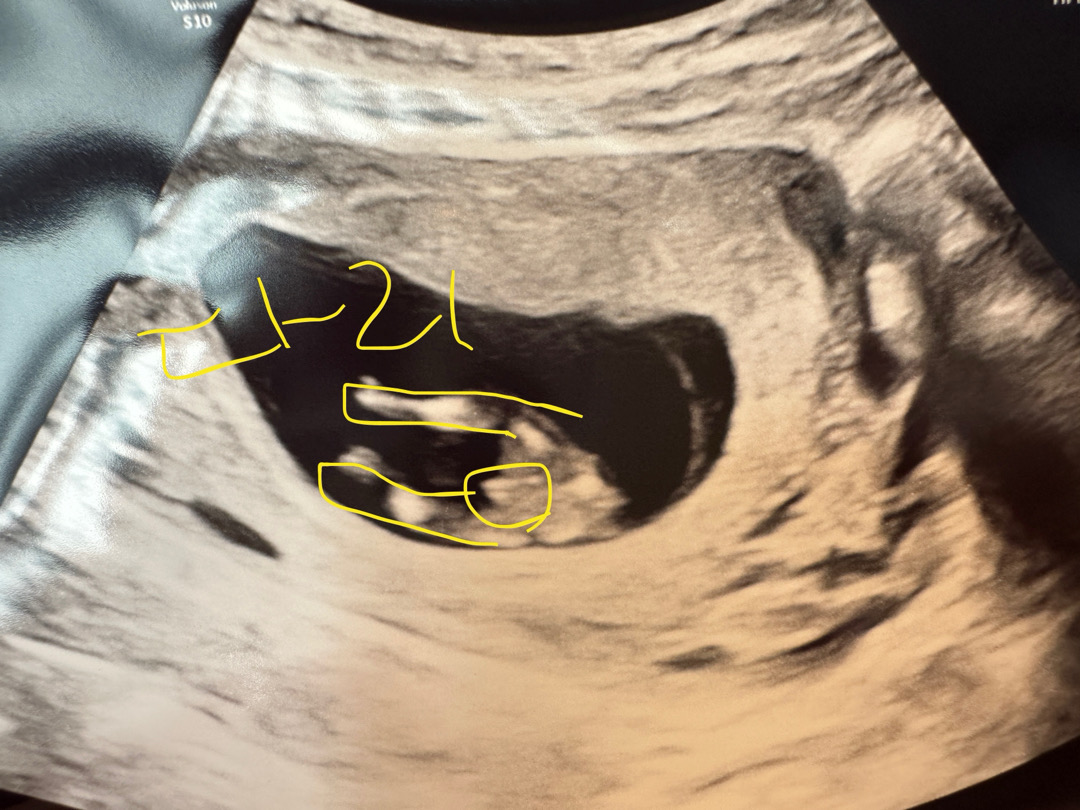

11주차인데 의사선생님이 아들암시를 주셨는데

의사선생님이 다리사이에 뭐가 달려있네요! 하시면서 그래도 아직은 잘몰라요~ 하셨는데 11주차에 확인이되나요!? 아들일까요?! 아들딸상관없이 건강하게 태어나주면 너무 고맙겠어요! 이글보시는 분들 모두 행복하시구 순산하세요❤️

저도11주차에는 저렇게나왔어요~아직모른데요~그래서 기다려보는중이에요

저는 12주차에 딸같다하샸는데 14주에 아들확정났어요 ㅋㅋㅋ 그때는 확실하지않나봐요!

아직 잘 모르는게 맞을거에요~ ㅎㅎ 초기엔 남아 여아 구분없이 비슷하다가 나중에 바뀐다고 하더라구요~